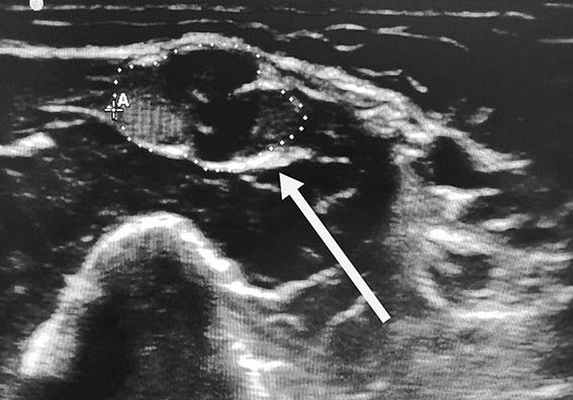

Клиническое наблюдение. Мальчик В., 2010 года рождения, с неотягощенным семейным анамнезом и без особенностей раннего развития. В возрасте 6,5 года мать впервые отметила, что ребенок без видимых причин начал прихрамывать на левую ногу. Неврологом в поликлинике было предположено поражение левого седалищного нерва, для уточнения генеза которого ребенок был направлен на УЗИ, которое не выявило изменений на доступном визуализации отрезке нерва.

При осмотре обращали на себя внимание слабость (до плегии в мышцах тыльного сгибания стопы) и гипотрофия мышц, иннервируемых левым пояснично-крестцовым сплетением (четырехглавая мышца бедра, бицепс бедра, группа мышц, приводящих бедро, большая ягодичная мышца, передняя большеберцовая, икроножная, короткий разгибатель пальцев), а также слабость удерживающих лопатку слева мышц: широчайшей, зубчатой, надостной, подостной (рис. 1). Рис. 1. Пациент В., 7 лет. Клиническая оценка мышечной силы. а — отсутствие тыльного сгибания левой стопы; б — сохранность силы мышц подошвенного сгибания стопы; в — слабость мышц, удерживающих лопатку слева. Сухожильные рефлексы не вызывались только с левой ноги. Нарушения чувствительности ограничены зоной иннервации левого пояснично-крестцового сплетения. В остальном неврологический статус был без особенностей: менингеальных симптомов нет, движения глазных яблок в полном объеме, нистагма нет, сила мимической мускулатуры 5 баллов, лицо симметричное, сухожильные рефлексы, кроме ахиллова и коленного слева, в том числе, рефлекс с ости лопатки нормальной живости и симметричные, патологических стопных знаков нет. Координаторные пробы: пальценосовую пробу выполняет удовлетворительно.

Результаты осмотра, УЗИ периферических нервов и ЭМГ констатировали поражение на уровне пояснично-крестцового сплетения. Для уточнения причины изменений проведено МРТ с контрастным усилением гадолинием, обнаружено увеличение нервных стволов и накопление контрастного вещества в пояснично-крестцовом сплетении (рис. 2). Рис. 2. Тот же пациент. МРТ пояснично-крестцового сплетения в режиме Т1 с контрастным усилением гадолинием. МРТ плечевого сплетения не выявило изменений.